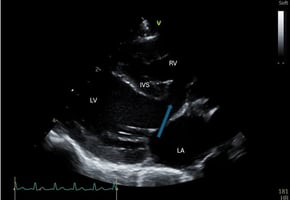

Feline congenital heart disease: understanding the clinical signs and managing care

Acquired heart disease in cats is relatively common in general practice, reported to affect about 15...

17 min read